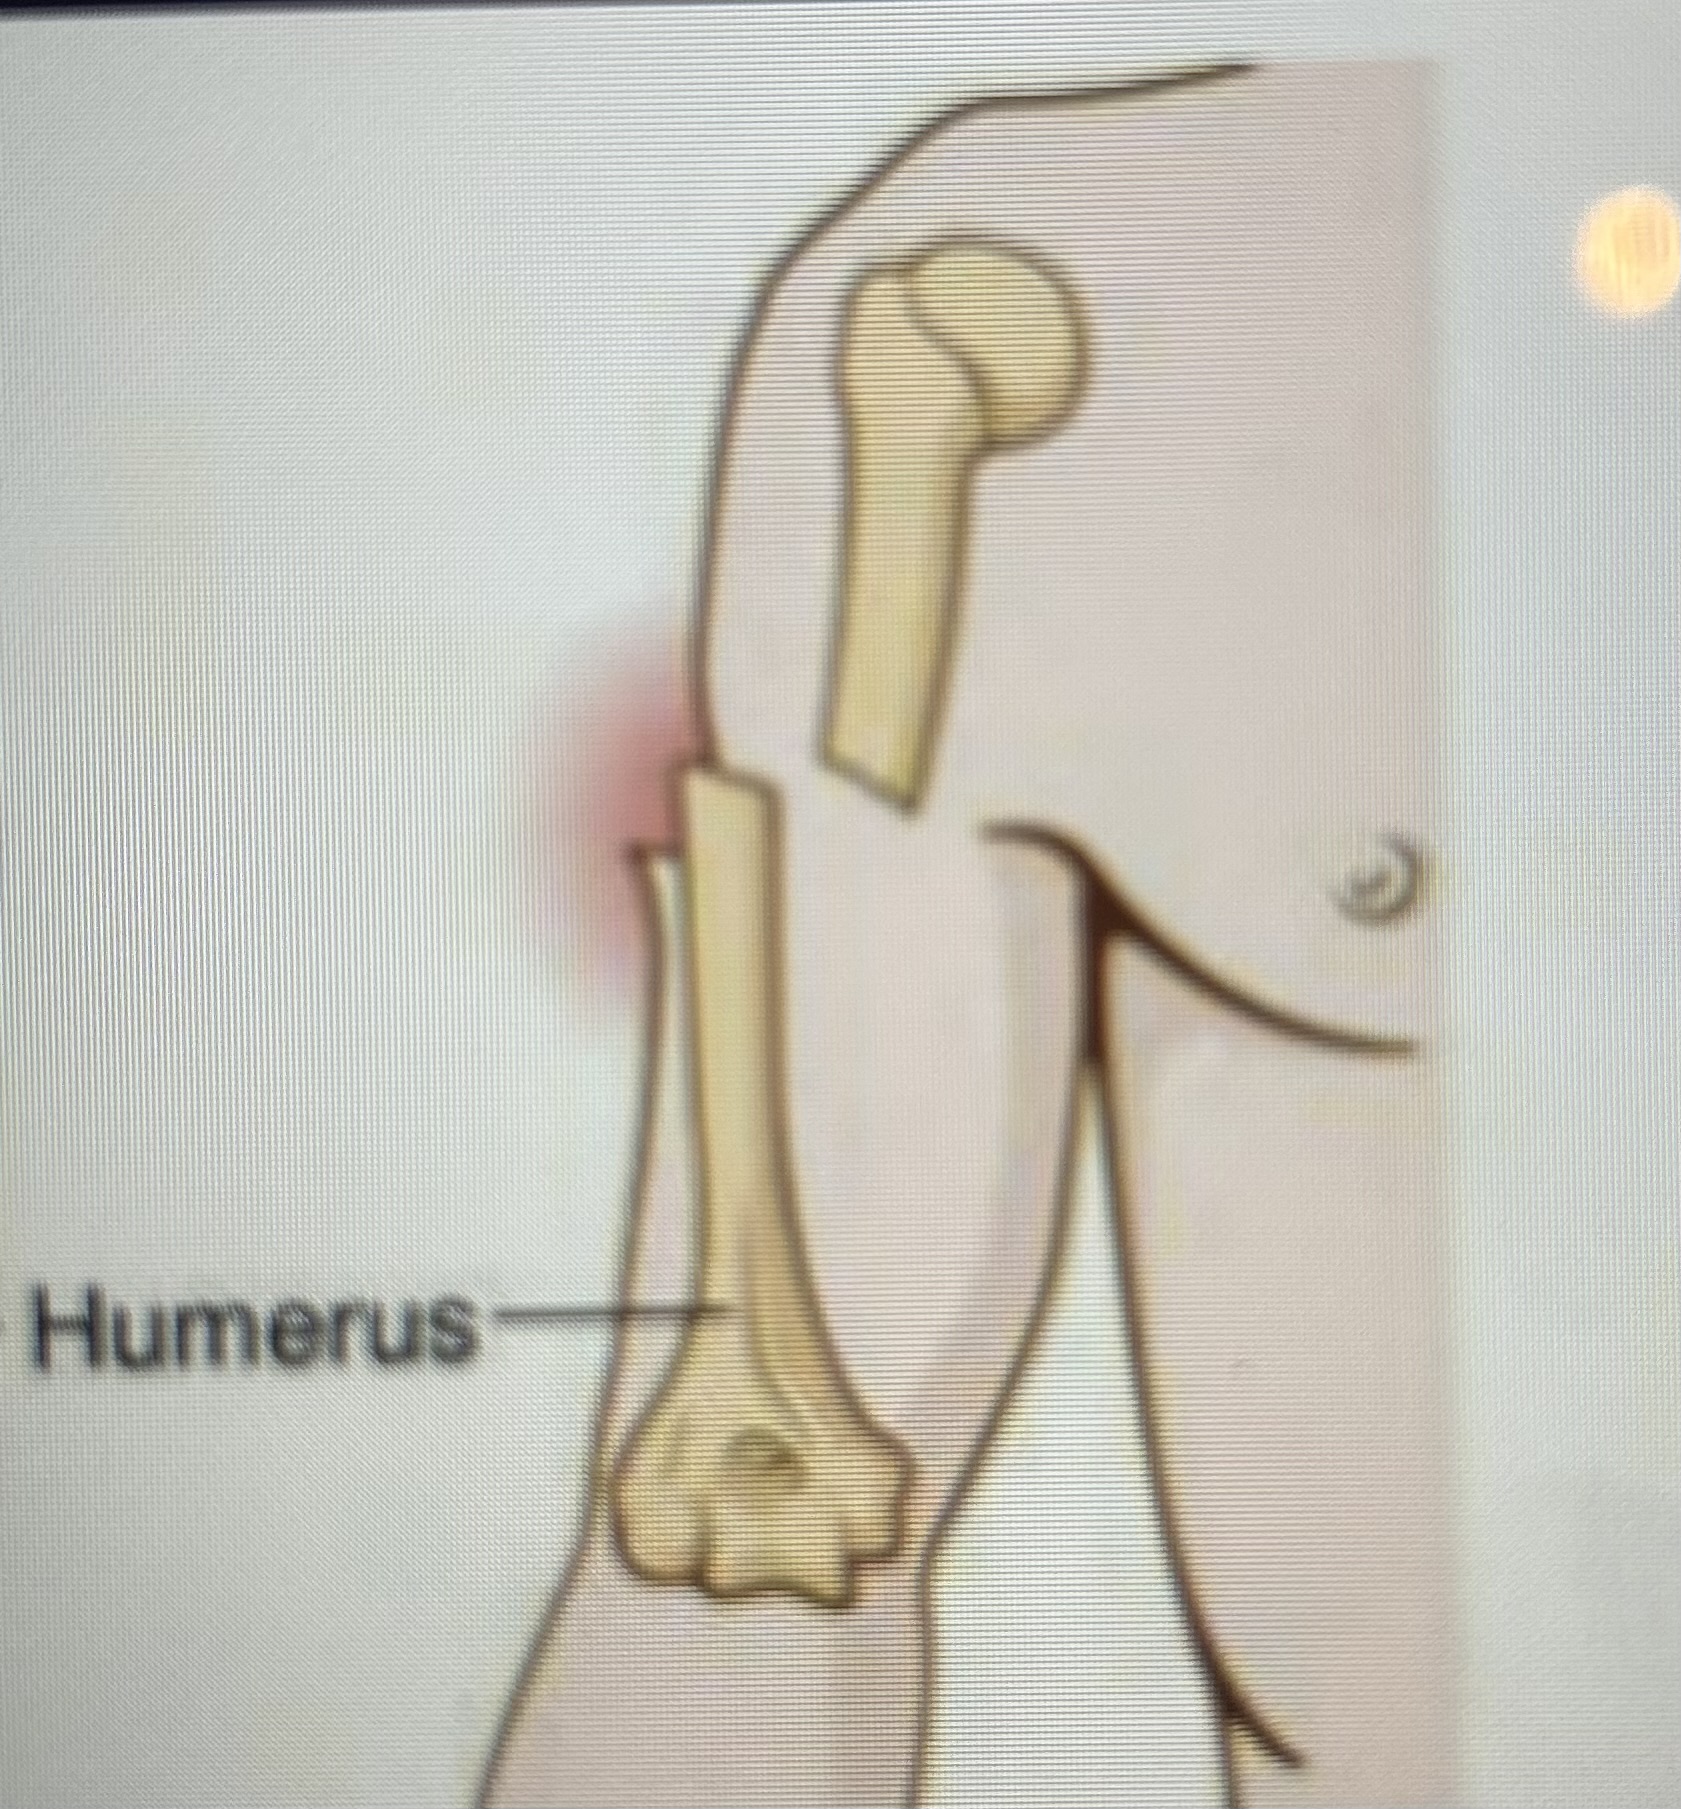

What type of fracture is this?

Compound/open fracture